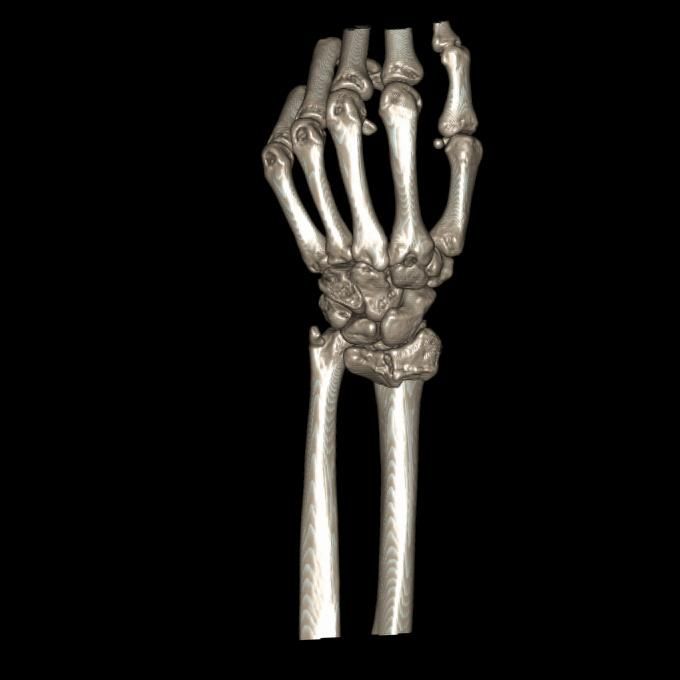

CT및 엑스레이는 12월 골절 당시 입니다

• 2번 째 사진

• 제공해 주신 영상들을 확인했습니다. MRI는 2023년 부분파열 당시 촬영본이고, 단순 방사선 및 CT는 2025년 12월 골절 당시 영상으로 이해하고 검토하겠습니다.

2023년 MRI 영상을 보면, 삼각섬유연골복합체(Triangular Fibrocartilage Complex, TFCC)에 전반적인 신호 변화와 함께 척골 부착부 근처의 손상 소견이 확인됩니다. 당시 봉합술을 시행한 것은 임상적으로 타당한 판단이었습니다. 이후 경과가 양호하다가, 2025년 12월 요골·척골 원위부 골절이 발생한 점이 현재 상황의 핵심입니다.

현재 상황을 종합적으로 보면, 폐쇄성 골절 후 금속 플레이트가 삽입된 상태에서 4월 이후 TFCC 부위 통증이 급격히 악화된 것은 단순한 염증 반응만으로 설명하기 어렵습니다. 골절 후 요척골 관계(distal radioulnar joint, DRUJ)의 정렬 변화, 플레이트 자체에 의한 기계적 자극, 또는 기존 봉합 부위의 재파열 가능성 모두를 고려해야 합니다. 플레이트가 있어 MRI를 아직 시행하지 못하셨다고 하셨는데, 이 부분이 현재 진단 판단의 가장 큰 제한점입니다.